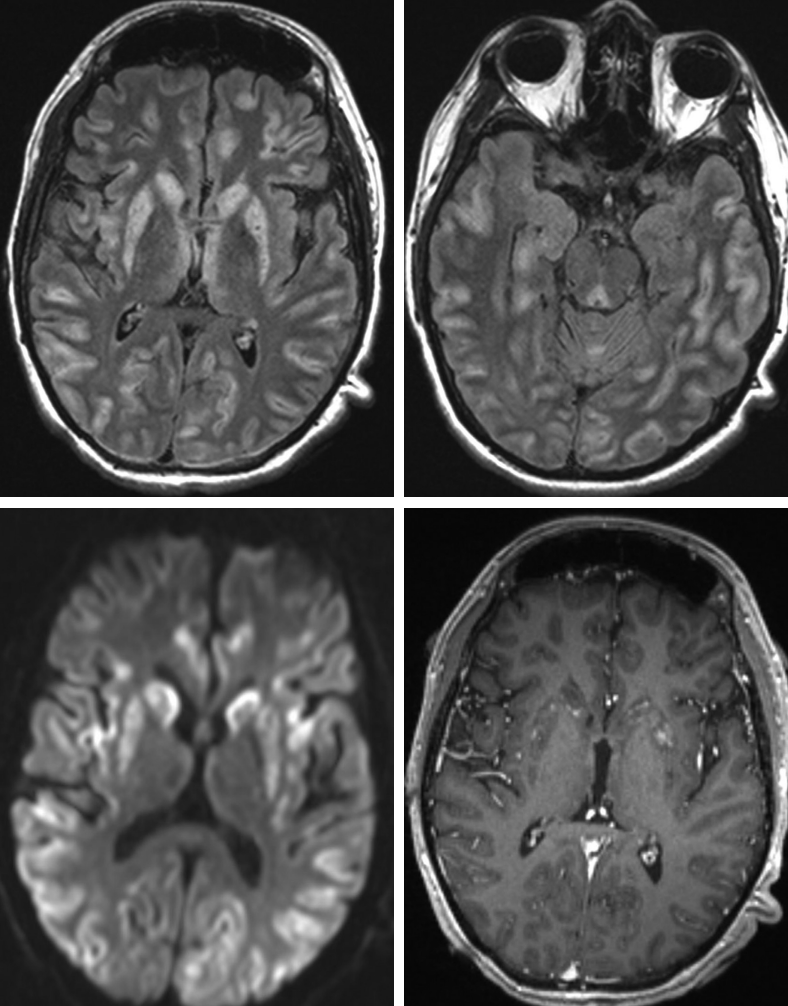

🔷35 y/o F w/ history of Li Fraumeni syndrome presents w/ intermittent left sided weakness and pain. The feeling is of heaviness, difficulty w/ grip, dropping objects and frequent falls. Episodes last for weeks to months. What is your diagnosis? 🧠

#Neurology #MRI #MedEd #medicine #neurosurgery #radres #futureradres #FOAMed @TheASNR

@daniel_gewolb TP53 mutation syndrome. I’d say multifocal GBM. Thanks for sharing

<What's your diagnosis?>

20 yo Male w/ recurrent neuro sx x12y:

Initial episode @ 8 yo → dx'd viral encephalitis

Recent: 5d GTC sz

Sx include: GTC sz, choreoathetosis, dystonia, hypotonia, apraxia, ataxia

All negative: LP, infectious/rheum w/u, mito panel, muscle bx

#Rdiag